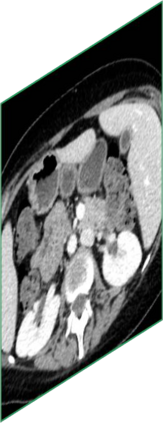

Due to the constraints of the imaging device and high cost in operation time, computer tomography (CT) scans are usually acquired with low intra-slice resolution. Improving the intra-slice resolution is beneficial to the disease diagnosis for both human experts and computer-aided systems. To this end, this paper builds a novel medical slice synthesis to increase the between-slice resolution. Considering that the ground-truth intermediate medical slices are always absent in clinical practice, we introduce the incremental cross-view mutual distillation strategy to accomplish this task in the self-supervised learning manner. Specifically, we model this problem from three different views: slice-wise interpolation from axial view and pixel-wise interpolation from coronal and sagittal views. Under this circumstance, the models learned from different views can distill valuable knowledge to guide the learning processes of each other. We can repeat this process to make the models synthesize intermediate slice data with increasing inter-slice resolution. To demonstrate the effectiveness of the proposed approach, we conduct comprehensive experiments on a large-scale CT dataset. Quantitative and qualitative comparison results show that our method outperforms state-of-the-art algorithms by clear margins.